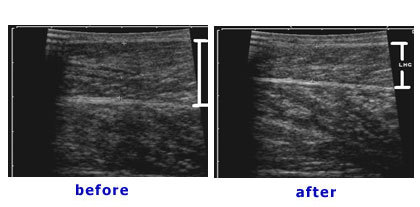

病例八:下圖病例術前小腿圍為36公分(左圖),做完腓腸肌及比目魚肌部份切除手術及小腿抽脂後三週,小腿圍已經變為32公分(右圖)。膝蓋後方的疤痕會漸漸變淡。下左圖是病人術前內側腓腸肌的超音波圖,二個箭頭間是內側腓腸肌,有二公分厚。

術後檢查內側腓腸肌變為一公分(下右圖)。